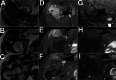

Multifocal desmoid-type fibromatosis (DTF) is very rare and usually regional. We report three cases that initially appeared to be multifocal, but subsequent detailed imaging revealed unsuspected tracking along nerves in two cases. This neural spread is reminiscent of neuromuscular choristoma (NMC), a rare developmental lesion in which mature skeletal muscle cells, or rarely smooth muscle cells, infiltrate and enlarge peripheral nerves. NMC is frequently associated with DTF. These two cases suggest that DTF spread along nerves and appeared as distinct multifocal lesions while actually being contiguous. The third case was felt to represent true multifocal tumor development, possibly due to tumor seeding at the time of chest surgery. The relationship of DTF to NMC is discussed.